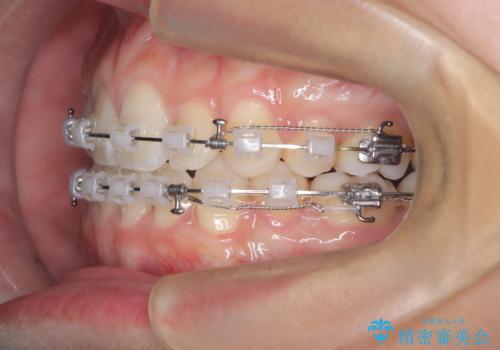

- 治療計画

上下左右の第一小臼歯を抜歯し、クリアブラケット(白い装置)とメタルワイヤーを使用して矯正を開始。初期には犬歯のアーチ内への整列を優先し、中盤からは前歯と奥歯の咬合関係の調整を進めました。審美性に優れた装置を使用したことで、治療中も目立ちにくく、見た目へのストレスが少ない点も評価されています。全体の治療は1年半で完了し、見た目・噛み合わせともに大きく改善。患者本人も「短期間でここまで変わるとは思わなかった」と満足されていました。